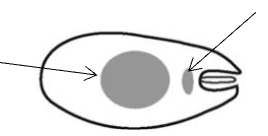

What tryponosome cell form is this?

Amastigote

Promastigote

Epimastigote

Trypomastigote